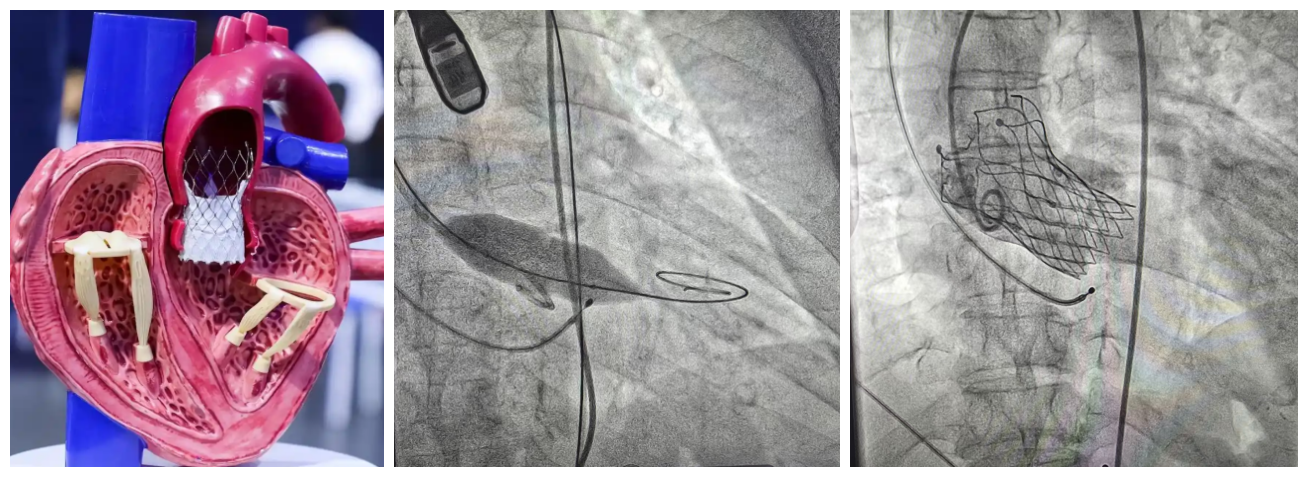

扬子晚报网12月11日讯(通讯员 刘柳 记者 万凌云 姜天圣)近日,镇江瑞康医院心血管内科在首席专家严金川教授的精心组织下,成功为一例重度主动脉瓣狭窄患者微创介入“换心门”。该技术称为经导管主动脉瓣植入术(TAVI)。

示意图

TAVI术中通过股动脉送入介入导管,首先采用球囊对患者重度狭窄的主动脉瓣膜进行预扩张,后将人工主动脉瓣膜送到拟释放位置,精确定位,人工瓣膜顺利释放,替换了原来重度狭窄伴钙化的瓣膜,术中经食道超声确认新的瓣膜位置准确、开放自如,患者主动脉瓣的功能得以恢复,手术成功。